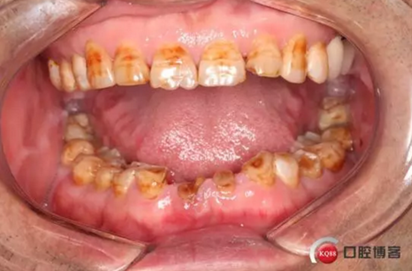

下圖是術前資料

患者,男性,47歲,全身情況良好,無手術禁忌,口內(nèi)因下前牙缺損松動不美觀來院。初診檢查時發(fā)現(xiàn)患者前牙深覆合,下頜32、42缺失。31、41松動二度,切緣磨耗嚴重,可探及髓腔,無保留價值。X-RAY檢查顯示:下頜前牙區(qū)寬度狹窄,咬合空間不足,無法行常規(guī)種植修復.